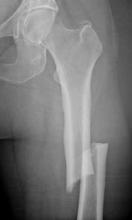

The society convened the international, multidisciplinary task force to address reports of “atypical fractures of the subtrochanteric region of the hip and the femoral shaft” in patients on long-term bisphosphonate therapy. A statement issued by the society on Sept. 14 announcing the release of the report referred to it as “the most comprehensive scientific report to date” on this issue. The task force based its report on findings from a review of published and unpublished data, interviews with scientists at companies that manufacture these drugs, and Food and Drug Administration data.

The review included a review of 310 published case reports of patients (aged 36-92 years) with atypical subtrochanteric and femoral shaft fractures. Of these patients, 291 (94%) had been treated with bisphosphonates, mostly for osteoporosis. The median duration of treatment was 7 years, and most were treated for more than 5 years, according to the report, which points out that these fractures are rare, accounting for less than 1% of the overall rate of hip and femur fractures (J. Bone Miner. Res. 2010 Sept. 14 [doi:10.1002/jbmr.253]).

More than half of the patients with such femur fractures had experienced a prodrome of pain in the groin or thigh for weeks or months, and fractures were bilateral in more than 25% of the patients.